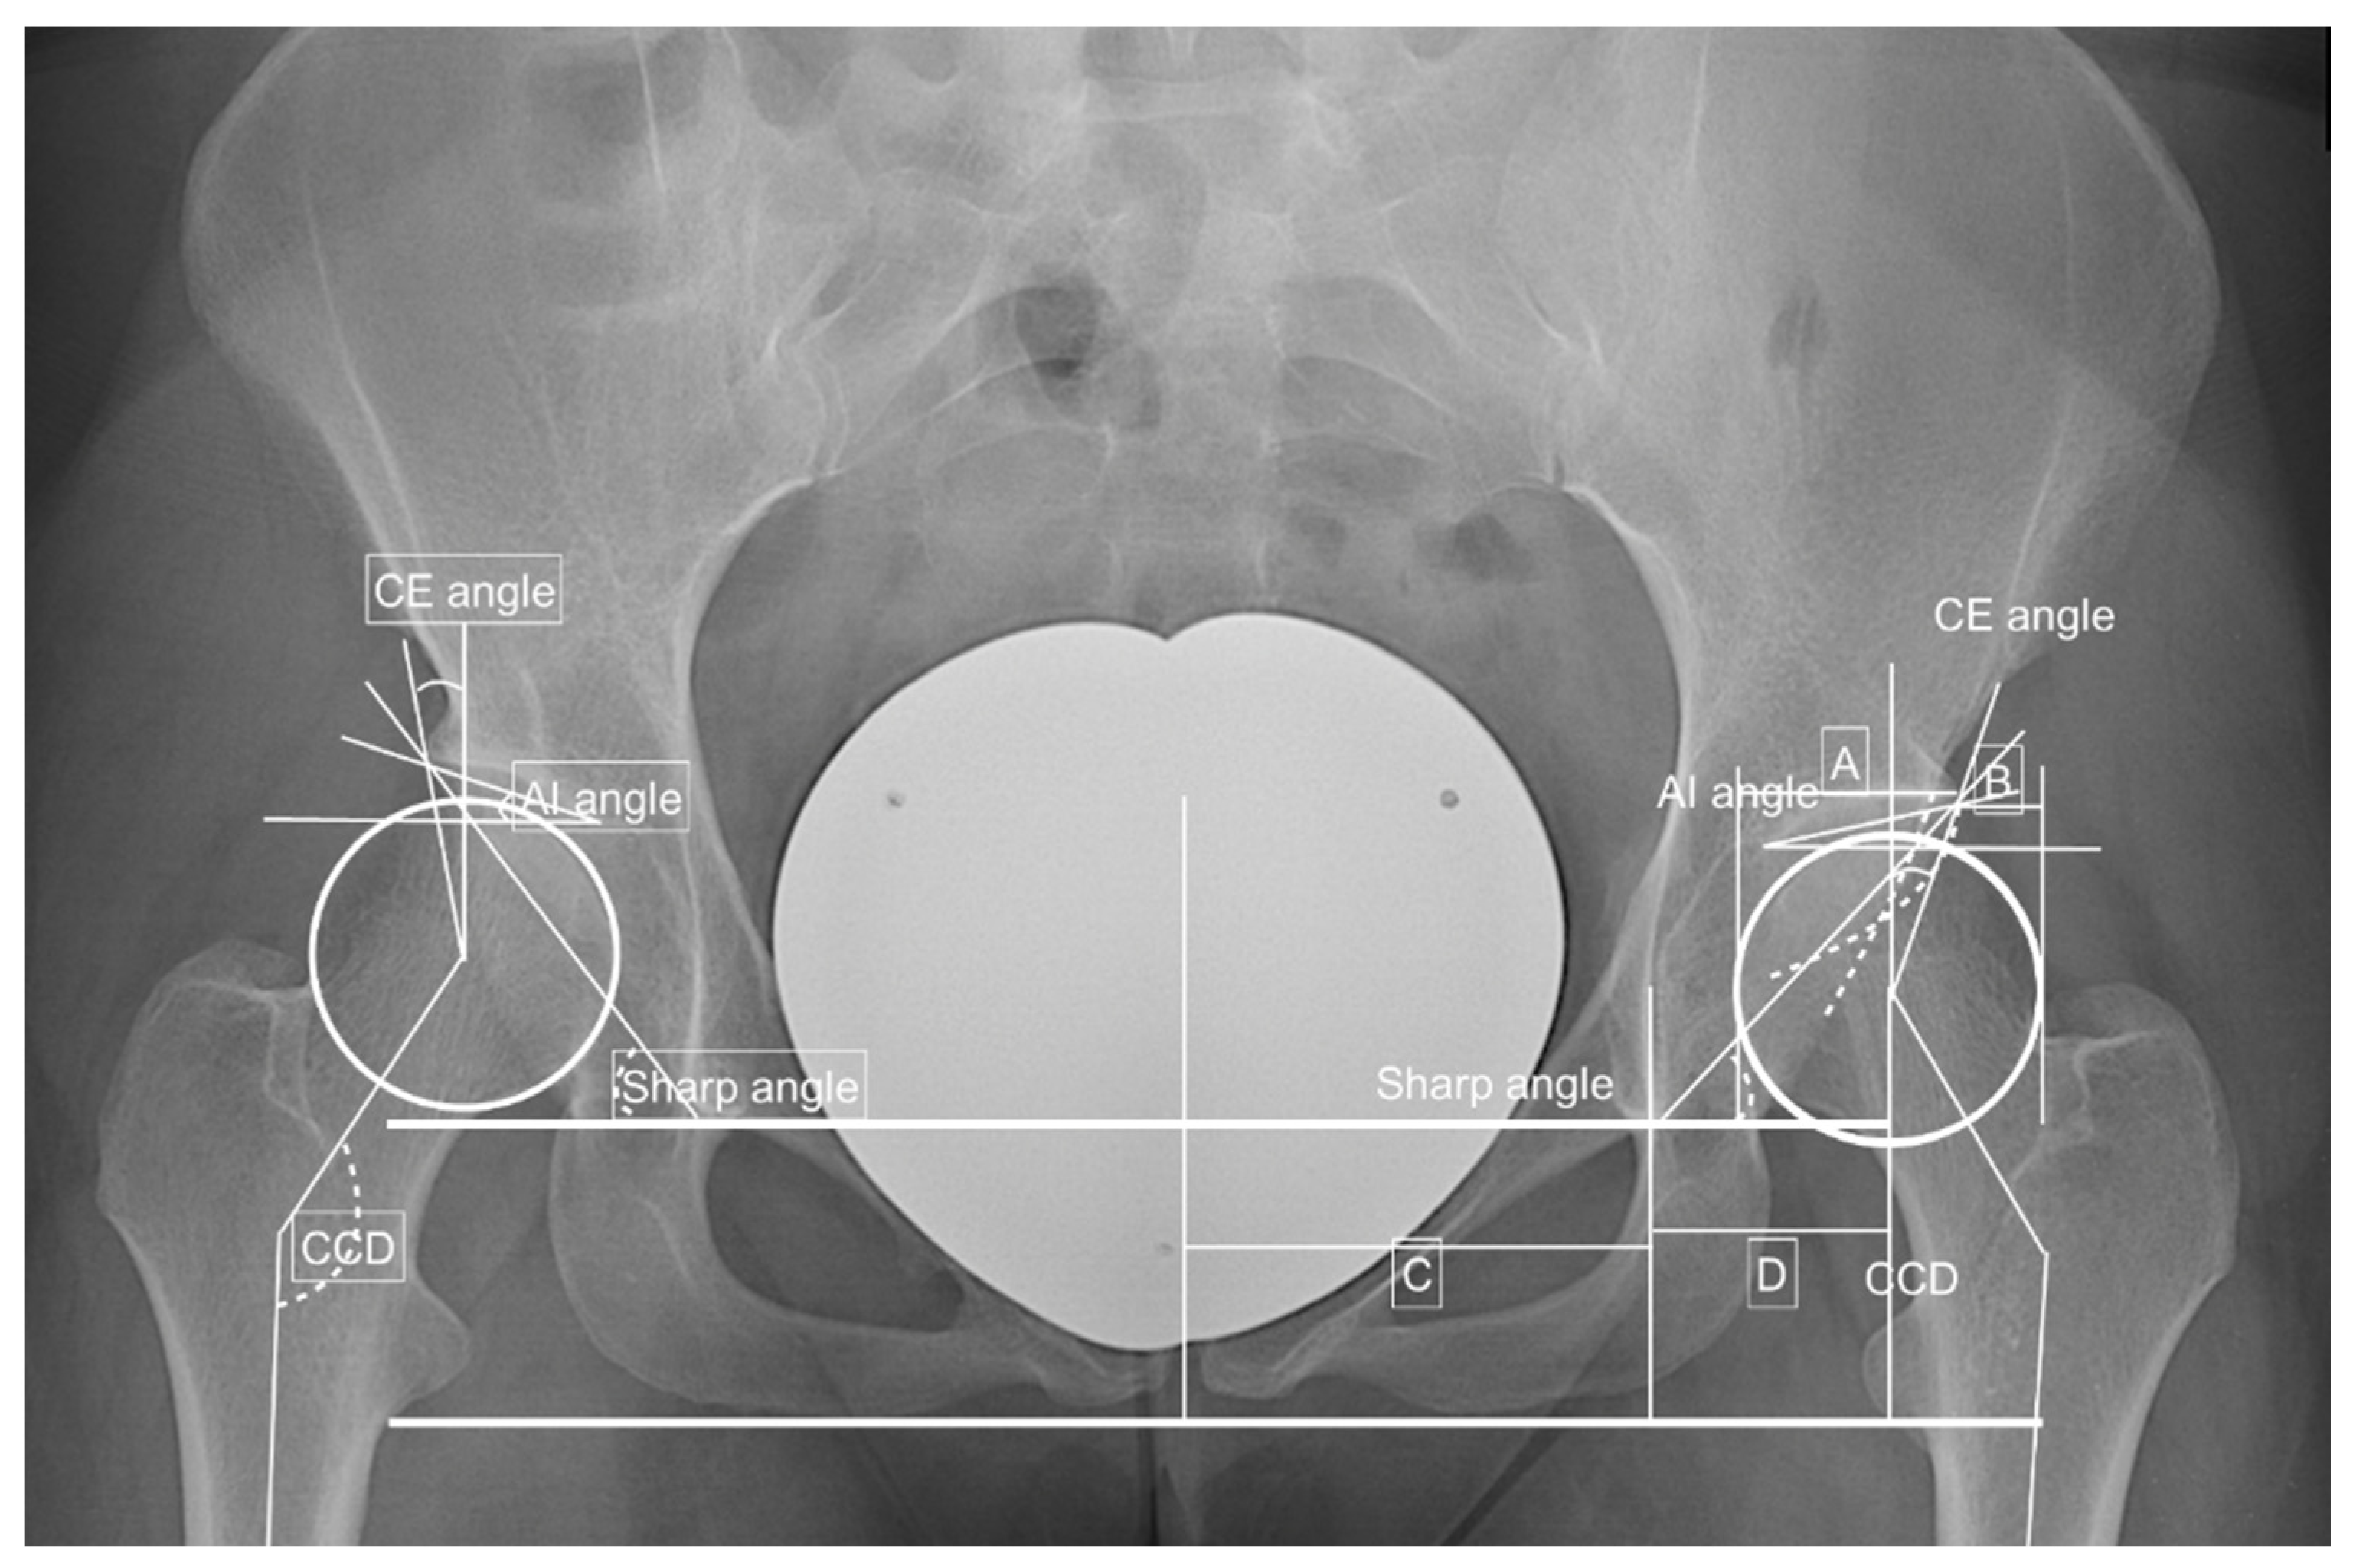

| CE angle (°) | 22.7 ± 5.8 | 0.002 | 0.968 | 21.0 ± 5.4 | 23.7 ± 5.8 | 0.050 |

| AI angle (°) | 11.2 ± 5.2 | 0.006 | 0.781 | 12.6 ± 6.3 | 10.3 ± 4.3 | 0.065 |

| Sharp angle (°) | 42.5 ± 3.7 | −0.005 | 0.894 | 43.3 ± 3.5 | 42.1 ± 3.8 | 0.148 |

| Hip lateralization index | 0.56 ± 0.06 | 0.617 | 0.590 | 0.57 ± 0.06 | 0.56 ± 0.06 | 0.214 |

| AHI | 23.2 ± 7.0 | 0.017 | 0.524 | 25.6 ± 5.7 | 21.9 ± 7.3 | 0.031 |

| CCD (°) | 133.0 ± 5.7 | <0.005 | 0.994 | 133.3 ± 6.4 | 132.8 ± 5.4 | 0.378 |

| Crossing over sign | 17 (32.7) | −0.194 | 0.184 | 4 (21.1) | 13 (39.4) | 0.091 |

| Kellgren–Lawrence score | 0.4 ± 0.5 | 0.015 | 0.909 | 0.4 ± 0.5 | 0.4 ± 0.5 | 0.488 |

| Alpha angle (°) | 100.0 ± 10.9 | −0.001 | 0.922 | 101.5 ± 10.0 | 98.8 ± 11.6 | 0.235 |

| Beta angle (°) | 57.0 ± 7.5 | 0.015 | 0.288 | 58.8 ± 7.8 | 55.7 ± 7.2 | 0.111 |